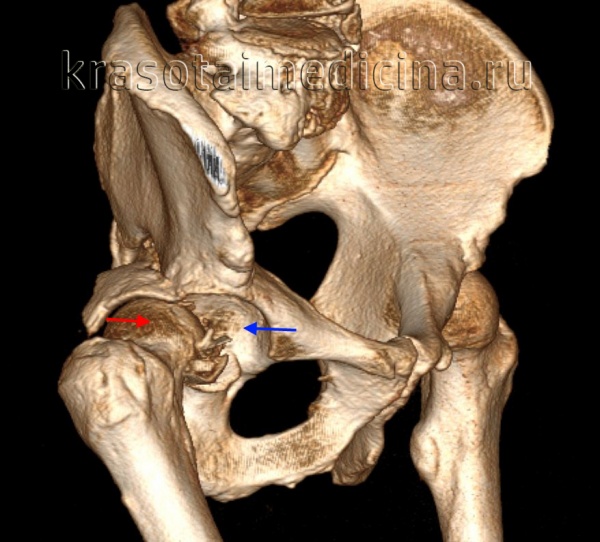

КТ таза. 3D-реконструкция. Красная стрелка – вывихнутая головка бедренной кости, синяя стрелка – «пустая» вертлужная впадина.

Рентгенография в дополнительных проекциях помогает оценить проксимальный сегмент бедренной кости с целью исключения переломов головки и шейки бедра. После вправления вывиха необходимо провести КТ, чтобы оценить результаты вправления, уточнить целостность вертлужной впадины и исключить наличие костных фрагментов в полости сустава. Вывихи изредка сопровождаются переломами головки бедра, которые должны быть соответствующим образом выявлены и устранены.